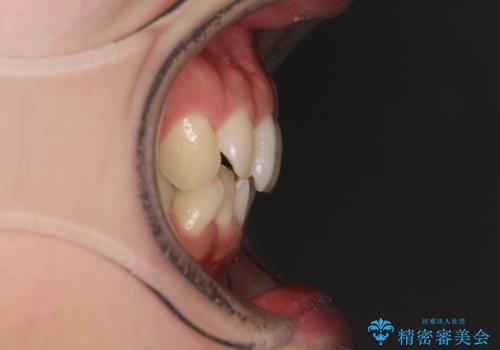

- 上下の前歯のデコボコを治したいとのことで来院された患者様です。

仕事柄、アジアの3つの国と地域を行き来するため、ワイヤー装置での治療は難しいと考えられました。

上下顎ともにIPR(歯と歯の間を削る)と歯列全体の拡大によって叢生が解消するように設計し、インビザラインにより治療を行うこととしました。